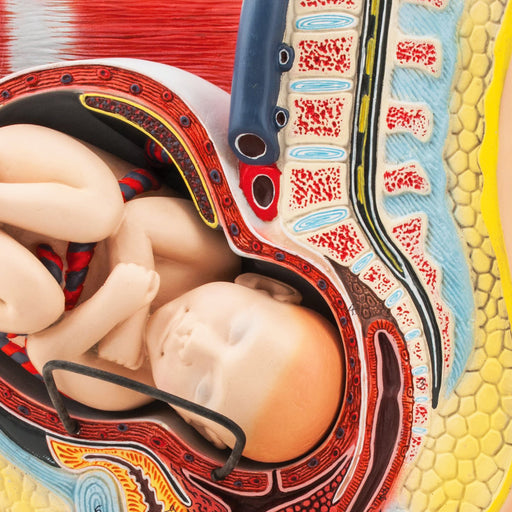

Female Pelvis with Baby, 13 Inch - Shows Pregnancy at 9 Months, Full Term - Removable Fetus - Eisco Labs

REMOVABLE FETUS || 3-dimensional female pelvis model showing the 9th month of pregnancy includes removable fetus MEDIAN CROSS-SECTION || For use ...